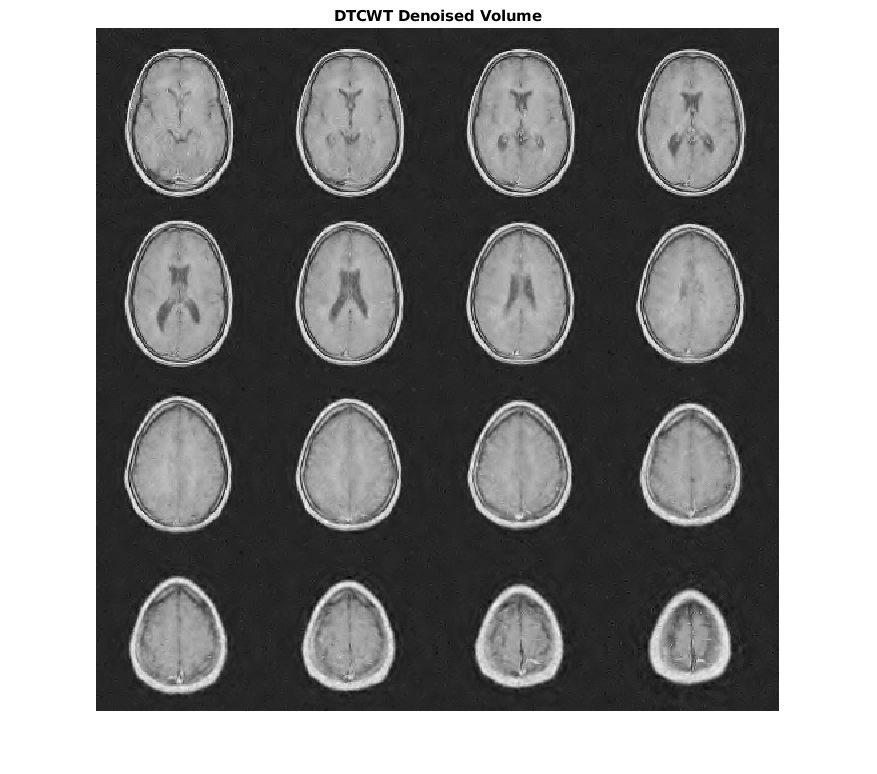

Чтобы продемонстрировать это, рассмотрите набор данных MRI, состоящий из 16 срезов. Гауссов шум со стандартным отклонением 10 был добавлен к исходному набору данных. Отобразите шумный набор данных.

load MRI3D montage(reshape(noisyMRI,[128 128 1 16]),'DisplayRange',[])

Обратите внимание на то, что исходный ОСШ до шумоподавления составляет приблизительно 11 дБ.

ans = 11.2997

Denoise набор данных MRI вниз к уровню 4 с помощью и DTCWT и DWT. Подобные длины фильтра вейвлета используются в обоих случаях. Постройте получившийся ОСШ в зависимости от порога. Отобразите denoised результаты и для DTCWT и для DWT, полученного в лучшем ОСШ.

[imrecDTCWT,imrecDWT] = helperCompare3DDenoising(origMRI,noisyMRI);

figure montage(reshape(imrecDTCWT,[128 128 1 16]),'DisplayRange',[]) title('DTCWT Denoised Volume')